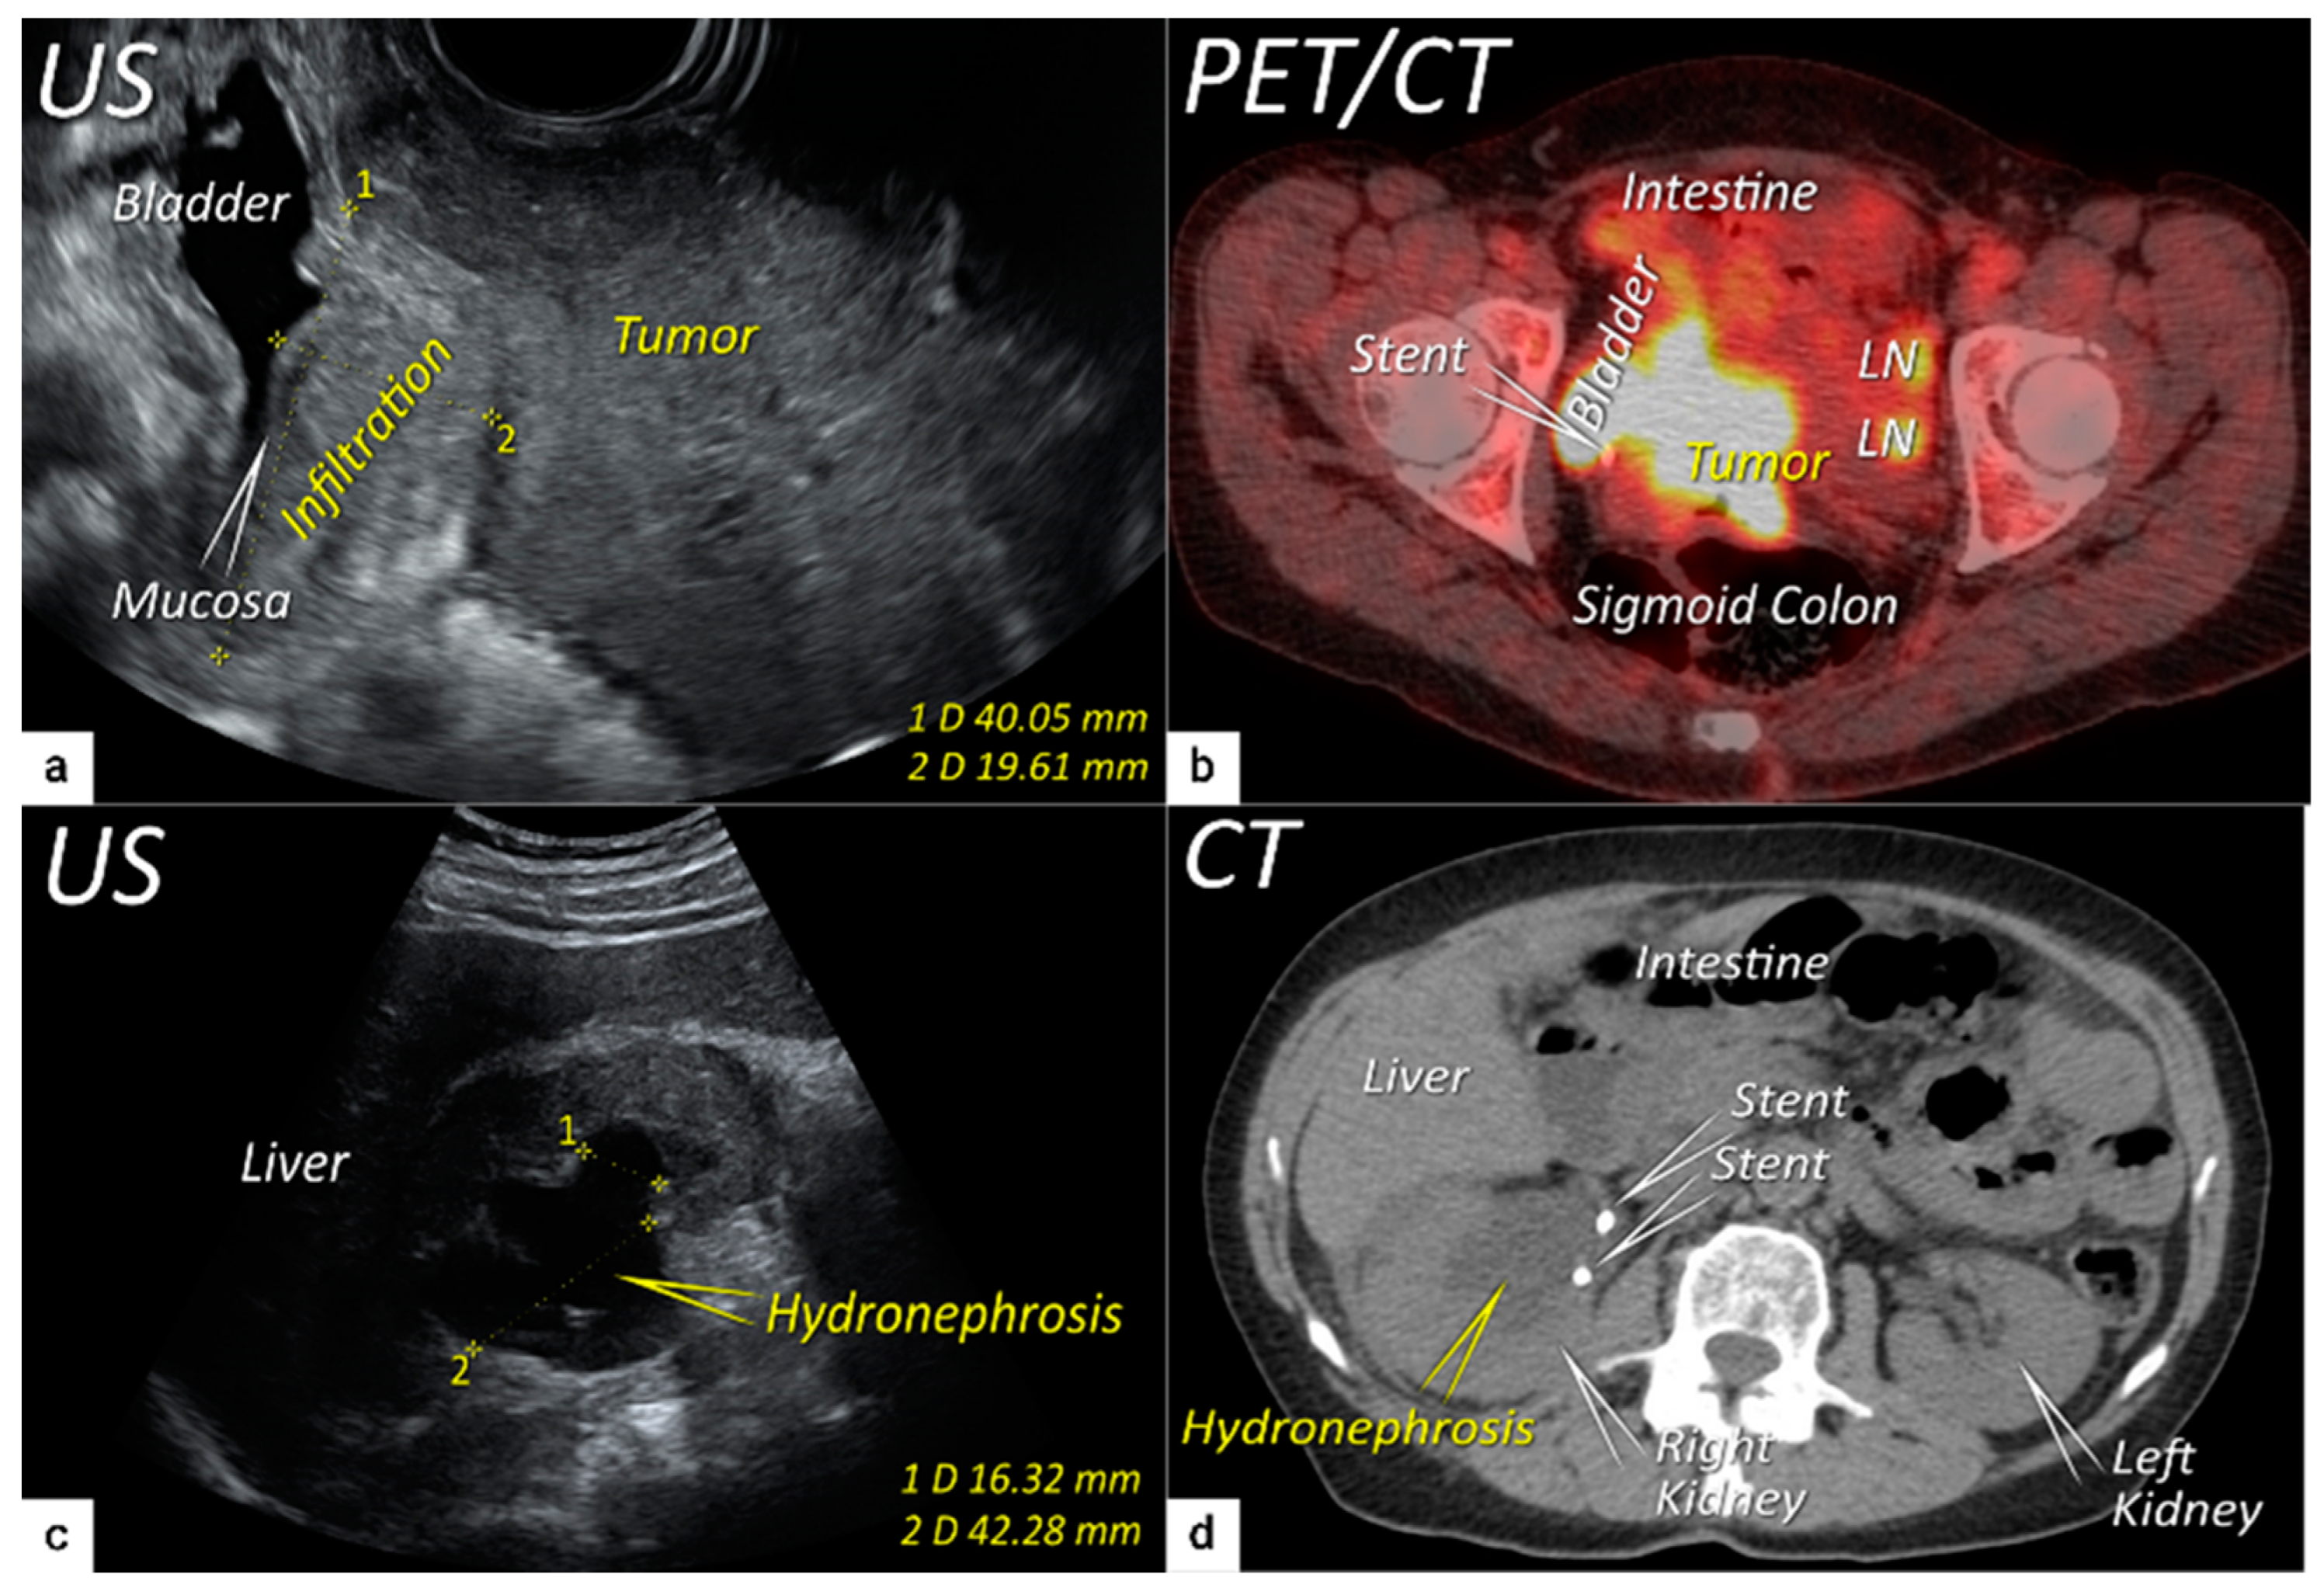

| T3 e | III e | Carcinoma involves the lower third of the vagina and/or extends to the pelvic side wall and/or causes hydronephrosis or non-functioning kidney | Tumour infiltration of the lower third of vagina or lateral pelvic side wall by US or MRI. Pelvic side wall infiltration is considered when the tumour causes hydroureter, infiltrates the obturator internus, piriformis, and levator ani muscles, encases the iliac vessels, or invades the pelvic bones on US or MRI. |

| T3b | IIIB | Tumour extension to the pelvic side wall and/or hydronephrosis or non-functioning kidney (unless known to be due to other cause). | US: Hypoechogenic tumour projections up to pelvic side wall +/− infiltration of iliac vessels, ureters, muscles, presence of hydronephrosis MRI: Hyperintense infiltration up to the pelvic side wall, loss of normal parametrial signal intensity and increased signal intensity in pelvic musculature due to tumour invasion seen on T2W-images. |

| T4 f | IVA f | Tumour invasion into the mucosa of the bladder or rectum (biopsy-proven) or into adjacent organs. | Tumour invasion into the mucosa of the bladder or rectum on imaging, confirmed by biopsy. US: Negative sliding sign, hypoechogenic tumour infiltration of bladder/rectal wall up to echogenic mucosa with polypoid tumour seen intraluminally. MRI: Focal or diffuse disruption of the normal T2-low signal intensity wall of the bladder/rectum, irregular or nodular wall, sometimes including an intraluminal tumour mass. Bulous edema sign, which is hyperintense thickening of the bladder mucosa on T2W images, is only an indirect sign of invasion and should not be regarded as T4 unless confirmed mucosal infiltration at cystoscopy. Infiltration of the posterior bladder wall without mucosal infiltration should not be regarded as T4a. |